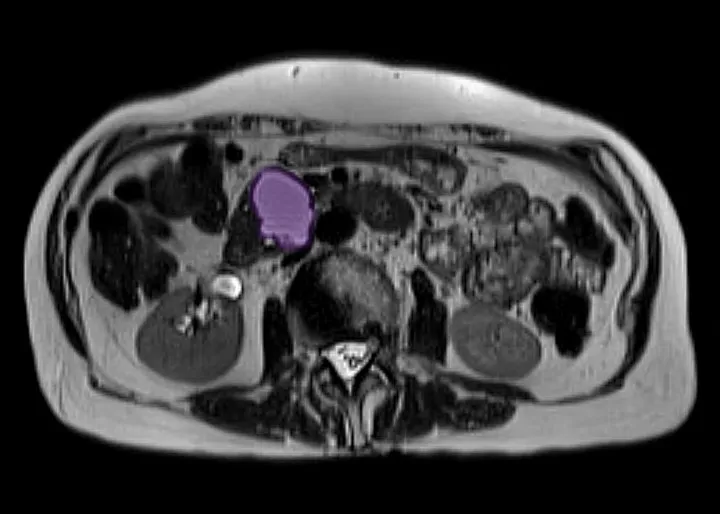

Für die Früherkennung von Bauchspeicheldrüsenkrebs bei Hochrisikopersonen haben sich zwei Hauptuntersuchungsmethoden etabliert: die Magnetresonanztomographie (MRT), oft kombiniert mit der Magnetresonanz-Cholangiopankreatikographie (MRCP), und die Endosonographie, auch endoskopischer Ultraschall genannt. Diese Verfahren ergänzen sich und liefern unterschiedliche, aber gleichermaßen wichtige Informationen über die Bauchspeicheldrüse.

Wie eine MRT der Bauchspeicheldrüse abläuft und was sie sichtbar macht

Bei einer MRT der Bauchspeicheldrüse liegen Sie in einer Röhre, während starke Magnetfelder und Radiowellen detaillierte Schnittbilder Ihres Körpers erzeugen. Die MRCP ist ein spezieller Teil der MRT, der die Gallenwege und Bauchspeicheldrüsengänge besonders gut darstellt. Diese Untersuchung ist nicht-invasiv und kann sehr feine Veränderungen im Gewebe der Bauchspeicheldrüse sowie Verengungen oder Erweiterungen der Gänge sichtbar machen, die auf frühe Tumore oder Vorstufen hindeuten könnten.